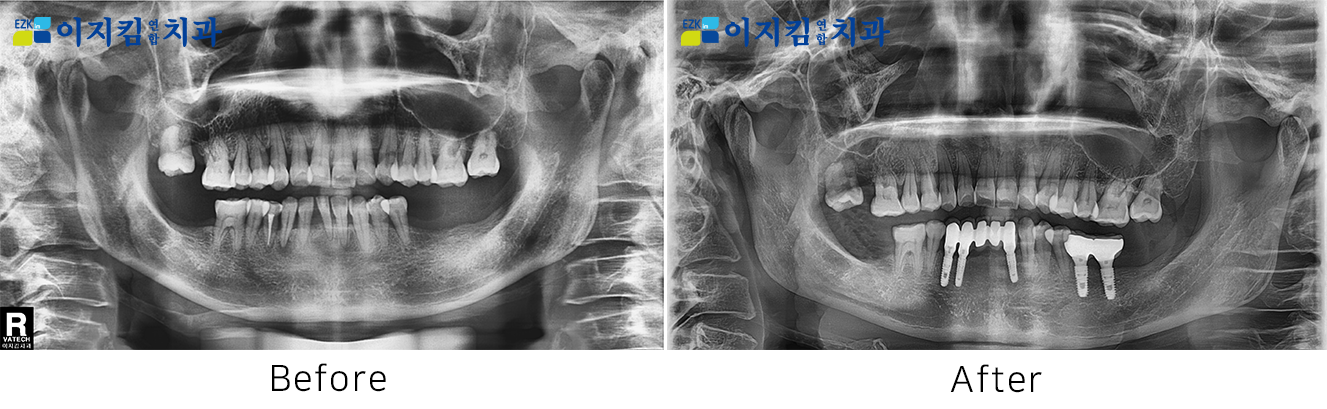

ÀÓÇöõÆ® Àü ¡¤ ÈÄ »çÁø

[

Á¶È¸¼ö : 2825

]